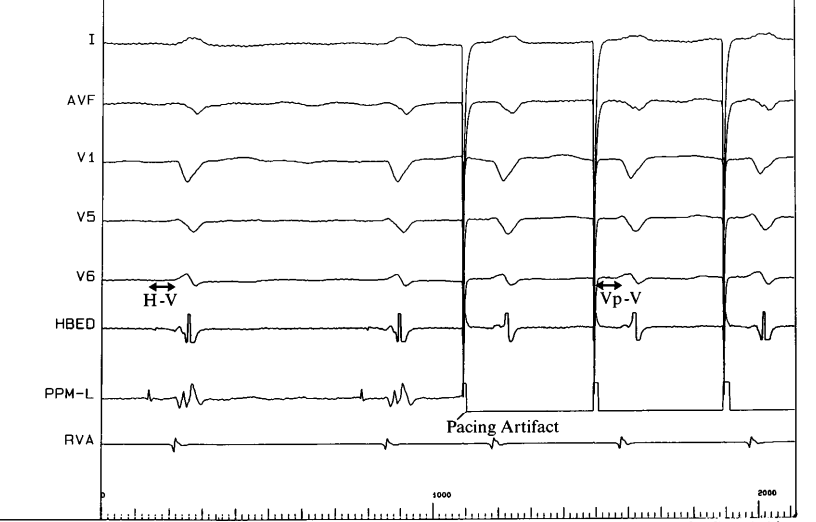

• His bundle pacing - selective and non-selective